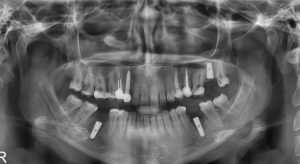

رادیوگرافی پانورامیک (OPG) 😁

تصویری جامع از هر دو فک، دندانها و مفصلهای فکی در یک تصویر، مناسب برای بررسی پوسیدگیها، دندانهای نهفته و درمانهای ارتودنسی. -